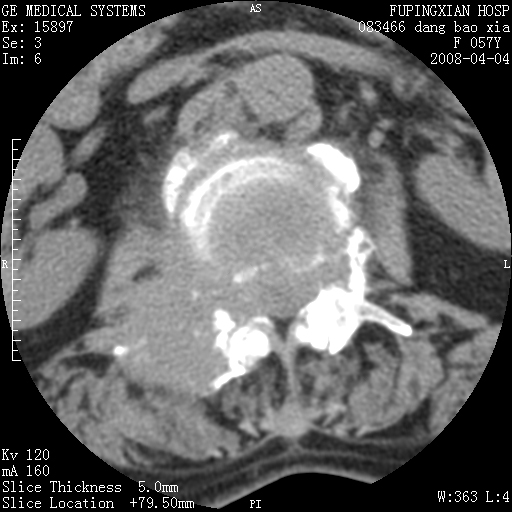

标题: CT12677:女性,57岁,疼痛数月。 [打印本页]

标题: CT12677:女性,57岁,疼痛数月。

椎体及附件骨质破坏同时伴软组织肿块,首先考虑恶性肿瘤。

病灶见多部位;转移瘤

查原发灶吧,考虑转移瘤。老年人出现骨肿瘤首先要除外转移瘤及骨髓瘤。

椎体及附件溶骨性破坏,周围巨大软组织肿块,首先考虑转移瘤。